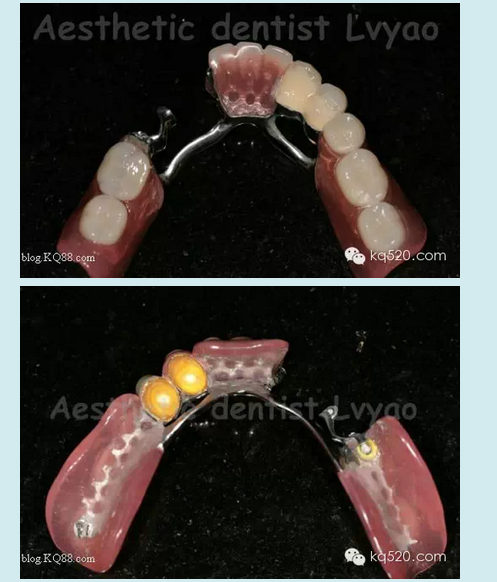

本病例在去年完成,患者是我的親人,現(xiàn)在修復(fù)體用的很好很舒適?;颊呱项M牙良好,下頜余留牙左下345良好,右下34有不同程度的牙槽骨吸收,右4松動(dòng)2度、右3松動(dòng)1度,臨床冠根比失調(diào)。原患者使用普通支架活動(dòng)義齒,現(xiàn)因基牙問(wèn)題等因素導(dǎo)致使用不佳,以保存基牙的原則等因素,本人設(shè)計(jì)了套筒冠與栓體栓道式附著體聯(lián)合應(yīng)用的修復(fù)技術(shù)。有關(guān)文獻(xiàn)報(bào)道,對(duì)于患者牙列缺損 少量基牙伴牙槽骨吸收或牙周病,不宜固定修復(fù)又對(duì)美觀(guān)、功能、舒適要求高??刹捎锰淄补谂c栓體栓道式附著體修復(fù)技術(shù)聯(lián)合的方法,此方法充分利用了栓體栓道式附著體固位力強(qiáng),義齒清洗時(shí)仍可維持垂直距離以及其固位體隱蔽和套筒冠技術(shù)的良好的基牙保護(hù)性能及可以在垂直及水平方向都能提高義齒的固位和穩(wěn)定性等優(yōu)點(diǎn)。有學(xué)者研究調(diào)查,發(fā)現(xiàn)套筒冠與栓體栓道式附著體聯(lián)合應(yīng)用的修復(fù)技術(shù)具有美觀(guān)、舒適、固位穩(wěn)定性良好、咀嚼效率高、保存保護(hù)基牙等優(yōu)點(diǎn)。實(shí)驗(yàn)表明牙周病患者能較快地適應(yīng)套筒冠義齒,咀嚼功能有所提高;套筒冠義齒具有良好的夾板固定效果,顯著降低牙周病患牙的松動(dòng)度,顯著減小牙周病患牙的牙周袋深度。

此病例正是如此,套筒冠主要的作用是保存維持了嚴(yán)重牙槽骨吸收的右下34基牙,改善了原基牙的臨床冠根比,縮短臨床冠高度大大減輕了對(duì)基牙承受的牙合力等其他應(yīng)力,減緩了牙槽骨的吸收,維持了基牙的使用壽命,再利用栓體栓道式附著體幫助,應(yīng)力分布更為均勻,從而修復(fù)后達(dá)到了非常好的效果。說(shuō)了那么多,還是看看病例照片吧:

有關(guān)修復(fù)體細(xì)節(jié)影像

套筒金沉積外冠效果更佳